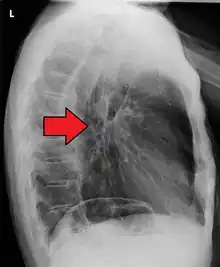

Although an occlusive tumor may be suspected on a barium swallow or barium meal, the diagnosis is best made with an examination using an endoscope. This involves the passing of a flexible tube with a light and camera down the esophagus and examining the wall, and is called an esophagogastroduodenoscopy. Biopsies taken of suspicious lesions are then examined histologically for signs of malignancy.

Additional testing is needed to assess how much the cancer has spread (see #Staging, below). Computed tomography (CT) of the chest, abdomen and pelvis can evaluate whether the cancer has spread to adjacent tissues or distant organs (especially liver and lymph nodes). The sensitivity of a CT scan is limited by its ability to detect masses (e.g. enlarged lymph nodes or involved organs) generally larger than 1 cm.[41][42] Positron emission tomography is also used to estimate the extent of the disease and is regarded as more precise than CT alone.[43] Esophageal endoscopic ultrasound can provide staging information regarding the level of tumor invasion, and possible spread to regional lymph nodes.

The location of the tumor is generally measured by the distance from the teeth. The esophagus (25 cm or 10 in long) is commonly divided into three parts for purposes of determining the location. Adenocarcinomas tend to occur nearer the stomach and squamous cell carcinomas nearer the throat, but either may arise anywhere in the esophagus.